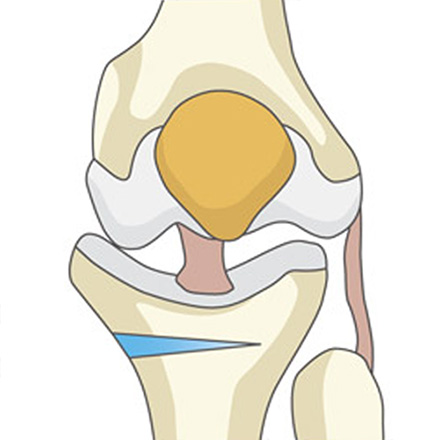

| 최소절개 무릎 절골술 (근위경골절골술) |

- 무릎 관절 자체는 건드리지 않고, 본래의 관절 구조물(연골, 인대 등)을 100% 보존하는 치료입니다. 환자 본인의 무릎을 더 오래, 더 편하게 사용할 수 있도록 기능을 회복시켜줍니다.

최소절개 무릎 절골술 과정

정강이뼈(경골) 윗부분을 약 3~5cm 절개한 뒤, 정강이뼈에 금을 냅니다.

정강이뼈 윗부분을 미세하게 벌려 인공뼈를 넣을 공간을 만들어줍니다.

벌려진 공간에 인공뼈를 넣어 틀어져 있던 다리 축을 정상 각도로 바로잡습니다.

바로잡은 각도가 잘 유지되도록 금속 플레이트와 나사로 단단히 고정합니다.